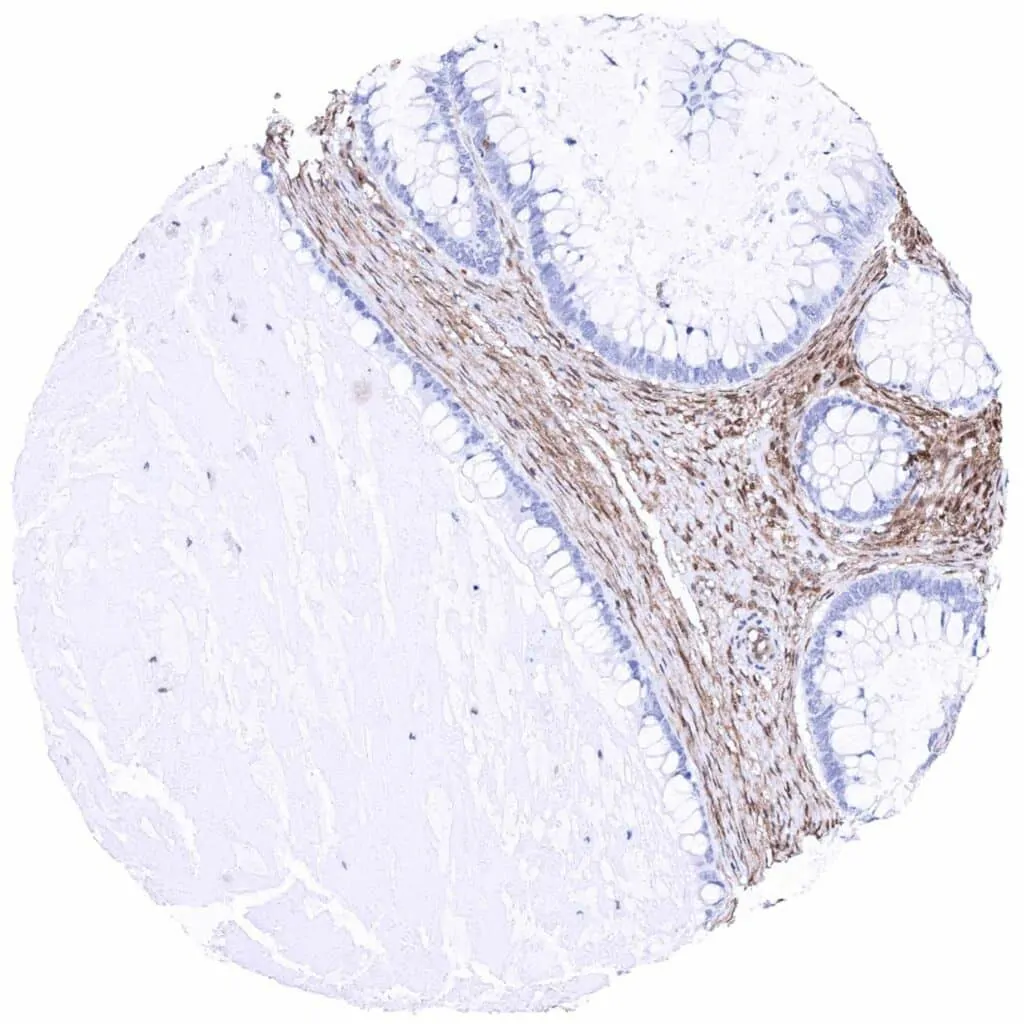

Colon – Colorectal adenocarcinoma with complete absence of MTAP staining in tumor cells. Intense MTAP staining of inflammatory and stromal cells